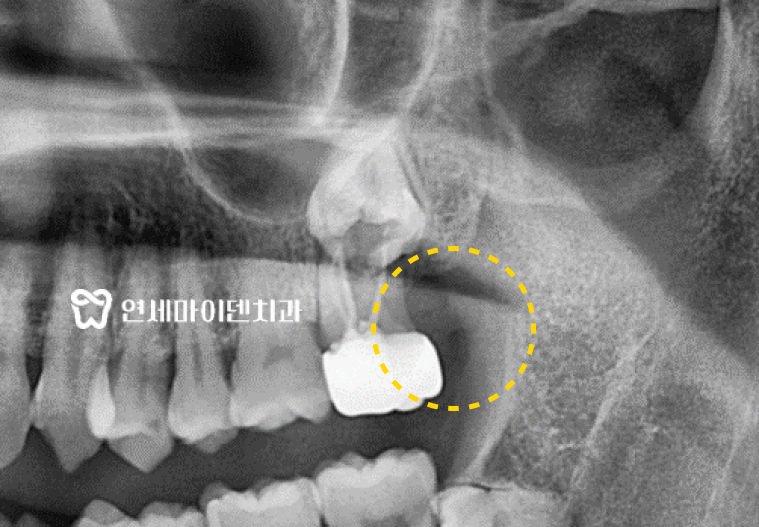

음식을 씹을 때 어금니 통증이 있던 50대 환자

이 환자분은 50대 환자분으로 음식을 씹을 때마다

왼쪽 아래 어금니에 통증이 느껴져 내원하셨습니다.

타 병원에서 신경치료를 여러 번 받았음에도 불구하고,

끝내 치근 수직파절로 인해 임플란트로 전환된 케이스인데요,이런 상황이 바로 임플란트를 선택해야 하는 상황 중 하나입니다.

첫 내원 당시, 왼쪽 아래 어금니 2개는 이전 병원에서 신경치료 후

각 크라운이 연결되어있는 ‘스플린트 크라운‘을 씌워놓은 상태였습니다.

재신경치료를 끝낸 후 6개월 후에 정기검진을 진행했습니다.

치료 직후에는 통증이 없었지만,

시간이 지나면서 다시 불편감을 느끼셨다는 환자분의 말씀.정확한 확인을 위해 엑스레이 촬영을 진행했습니다.

검진 결과, 재신경치료 한 어금니 2개 중

#37번 끝 치아의 뿌리 끝에 염증이 재발한 것을 확인했습니다.치아를 살리기 위해 재신경치료를 시도하지만

보존적 술식을 적용할 수 있는지 확인해보기로 했습니다.발치 후 발견한 뿌리 염증의 원인은?

문제의 어금니를 발치한 후 뿌리를 직접 살펴봤습니다.

위의 사진처럼 치아 뿌리에서 위쪽으로 올라가는

‘수직 치근파절’이 발견되었습니다.크랙이 없었다면 염증을 깨끗하게 제거해준 뒤,

치아 재식술이나 치근단 절제술과 같은 보존적 술식을 적용해볼 수 있었겠지만명확하게 크랙이 확인된 상황에서 발치하지 않으면

치아와 뼈가 재생되지 않고 염증이 점점 심해져 주변치아의 예후까지 위협할 수 있습니다.따라서 해당 치아는 발치 즉시 임플란트를 진행하기로 하였습니다.

임플란트 식립 시에는 임플란트를 식립할 위치와 각도가 매우 중요합니다.

수술 전 환자분과 상의 후 3D 네비게이션으로 모의 수술을 통해

임플란트를 식립할 위치를 정확히 설정했습니다.또, 발치 직후에는 기존에 있던 염증들을 깨끗하게 제거해야만

미세현미경을 통한 염증의 제거와 3D 네비게이션을 활용하여

발치 즉시 임플란트 식립을 진행하였습니다.식립 이후 잇몸 뼈가 잘 회복되는 것을 확인한 뒤

2차 임플란트 수술 후 최종 보철물까지 올려 치료를 마무리 했습니다.임플란트 수술 전, 고려해봐야 하는 것들